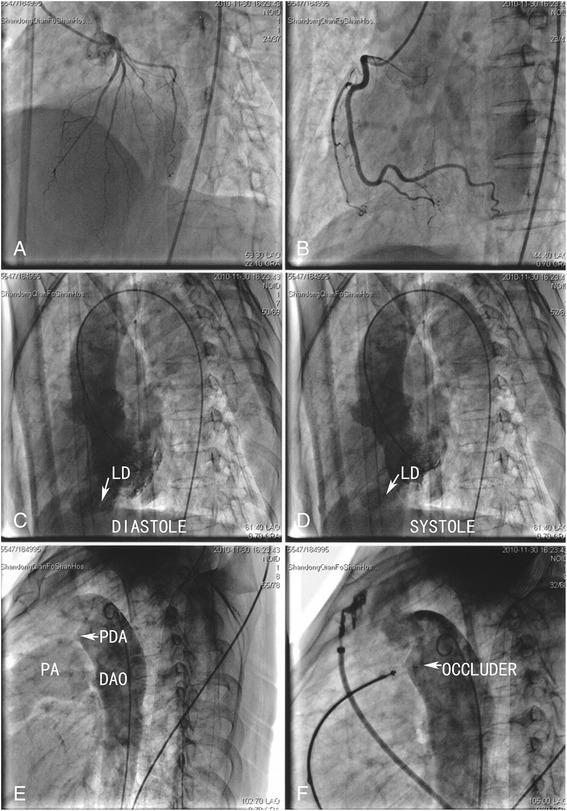

A 58-year-old woman was referred to our hospital because of complaints of chest pain and dyspnoea, mainly on exertion. An electrocardiograph on admission showed a q-wave in lead I, a Q-wave in lead aVL, and an abnormal T-wave in the limb leads and leads V4 to V6. A transthoracic echocardiograph revealed a PDA and a protrusion arising from the apex of the left ventricle. The diagnosis on admission was PDA and coronary artery disease with infarct aneurysm. To evaluate the source of the chest pain, further evaluations were performed. Coronary angiography showed no abnormal findings. Left ventriculography confirmed the presence of an apical contractile out-pouching. Based on these findings, we revised the diagnosis as LD associated with PDA. The patient underwent transcatheter occlusion of the PDA and was discharged 3 days later. Unexpectedly, transcatheter occlusion resolved the paroxysmal chest pain in this case.

一名58岁女性因主要在劳累时出现胸痛和呼吸困难而被转诊至我院。入院时心电图显示I导联有q波,aVL导联有Q波,肢体导联及V4至V6导联T波异常。经胸超声心动图显示有动脉导管未闭及左心室心尖部突出。入院诊断为动脉导管未闭和冠状动脉疾病伴梗死性动脉瘤。为评估胸痛的病因,进行了进一步检查。冠状动脉造影未发现异常。左心室造影证实存在心尖部收缩性膨出。基于这些发现,我们将诊断修订为与动脉导管未闭相关的左心室憩室。患者接受了动脉导管未闭的经导管封堵术,3天后出院。出乎意料的是,经导管封堵术解决了该病例的阵发性胸痛。